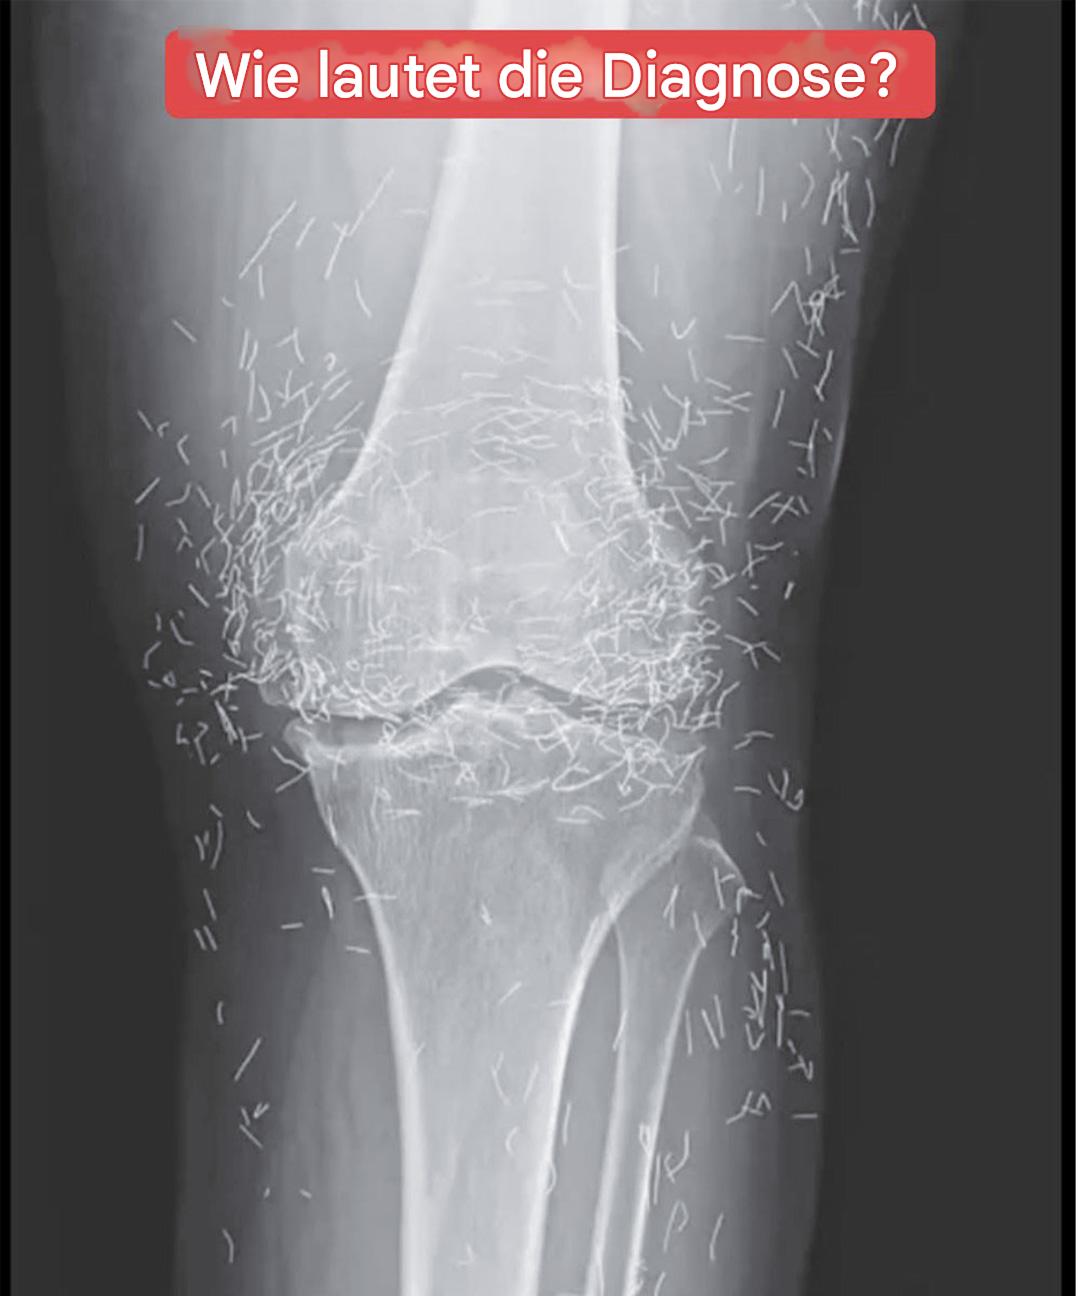

Stellen Sie sich vor, Sie lassen sich wegen Knieschmerzen röntgen und entdecken, dass Ihr Körper einen wahren Schatz birgt! So erging es einer 65-jährigen Frau, deren medizinische Aufnahmen eine unerwartete Erscheinung enthüllten. Was die Ärzte sahen, warf weit mehr Fragen auf, als es beantwortete. Und hinter diesem faszinierenden Bild verbirgt sich eine Praxis, die in Frankreich noch relativ unbekannt, weltweit jedoch weit verbreitet ist.

Während der Sitzungen wurden dieser Patientin Goldnadeln um ihre schmerzenden Gelenke eingeführt. Im Gegensatz zur herkömmlichen Methode, bei der sie nach der Sitzung entfernt werden, blieben diese Mikronadeln im Gewebe. Das Ziel? Die wohltuende Wirkung der Stimulation langfristig zu erhalten.

Diese Technik, die manchmal auch als „permanente Akupunktur “ bezeichnet wird, wird in einigen asiatischen Ländern noch immer praktiziert, insbesondere zur Linderung chronischer Schmerzen. Dabei werden winzige sterile Drähte aus Gold oder chirurgischem Stahl eingeführt , die an Ort und Stelle bleiben – manchmal jahrelang oder sogar ein Leben lang.

Bei einer routinemäßigen Röntgenuntersuchung entdeckten die Ärzte zu ihrer Überraschung Hunderte kleiner, glänzender Nadeln, die um seine Knie verstreut waren. Eine wahre medizinische Kuriosität, die sowohl Erstaunen als auch Vorsicht weckte. Denn obwohl Gold ein inertes und gut verträgliches Metall ist, ist die längere Anwesenheit von Fremdkörpern im Körper nie ungefährlich.

Laut Experten für medizinische Bildgebung können diese Nadeln bestimmte Körperbereiche auf Röntgenbildern verdecken und so die Diagnose anderer Probleme erschweren. Vor allem erschweren sie die MRT-Untersuchung erheblich: Es besteht die reale Gefahr, dass sich die Nadeln unter dem Einfluss des Magnetfelds bewegen und empfindliches Gewebe schädigen.